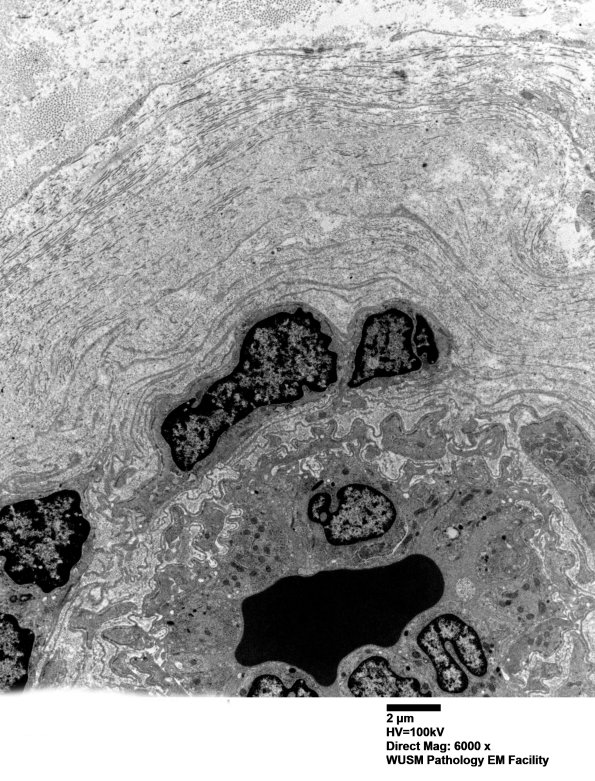

Thickening of this vessel wall consists of accumulated basal lamina fragments and collagen. Several individual inflammatory cells may be present. (electron micrographs) ---- Interpretation: There is no C5b-9 deposition and is clinically different from HIEM.